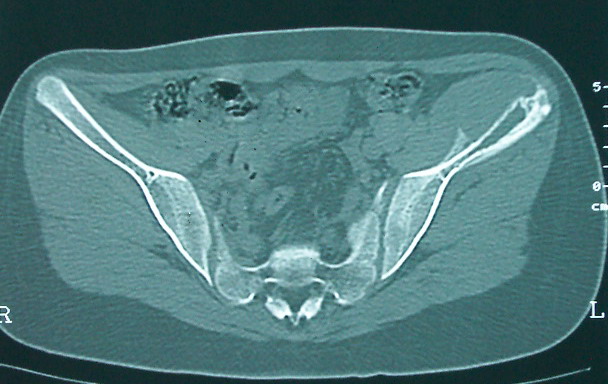

女 13岁 4月前有臀部肌肉注射史 3月前发热 最高体温38.5 2月前出现左髂骨疼痛 不剧烈能忍受 发热时高时低 按感冒治疗无好转 近日左髂骨疼痛加重 一星期前wbc 12.2 今日wbc9.5

左侧髂骨溶骨性骨质破坏,骨皮质侵蚀,灶周可见软组织肿块,支持考虑骨肉瘤可能性大。

髓腔起源,弥漫性溶骨性骨质破坏并软组织肿块,膨胀不明显,无显著钙化及瘤骨,有骨膜反应,结合年龄考虑恶性,尤文氏肉瘤可能性大。

鉴别:尤文氏肉瘤>毛细血管扩张型骨肉瘤>骨原发淋巴瘤>朗格罕氏细胞增生症>软黏纤>慢性骨髓炎>tb。

左侧髂骨溶骨性骨质破坏,骨皮质侵蚀,灶周可见软组织肿块

支持髂骨低毒性骨髓炎或骨结核:骨质破坏,髂腰肌明显肿胀,非长管状骨部位。

左侧髂骨溶骨性骨质破坏,骨皮质侵蚀,灶周可见骨膜反应及软组织肿块,支持考虑骨肉瘤可能性大。

骨质破坏+增生+软组织肿胀提示骨髓炎